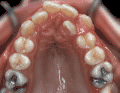

牙齒矯正,也稱牙齒正畸,俗稱“箍牙”,主要通過矯正裝置調(diào)整上下頜骨之間、上下牙齒之間、牙齒與頜骨之間以及相關(guān)聯(lián)的神經(jīng)和肌肉之間不正常的關(guān)系,終達(dá)到口頜系統(tǒng)穩(wěn)定、美觀的果。

數(shù)據(jù)分析表明,大約50%左右的矯正患者需要拔牙。很多病人不理解為什么為了矯正牙齒有時(shí)還需要拔除牙齒,而且這些牙齒都是健康牙齒,拔除了似乎很可惜。

拔牙矯正的原理和原因是什么?拔牙,是牙齒矯正中常見的矯正手段,原理是拔掉功能性不那么強(qiáng)的牙齒,為牙齒排齊提供可移動(dòng)的空間。

實(shí)際上做牙齒矯正,拔牙是很普遍、很成熟的矯正手段,這是因?yàn)橛行┤说难懒颗c骨量不匹配,造成牙齒畸形。因此在矯牙時(shí),可能需要拔掉一定數(shù)量的牙,以協(xié)調(diào)牙量與骨量的關(guān)系,解除牙列擁擠的狀況,減少畸形復(fù)發(fā)。

當(dāng)牙齒排列整齊,無擁擠現(xiàn)象狀況,但是牙性上頜前突、雙頜前突,要想矯治前突畸形,也需要拔牙矯治